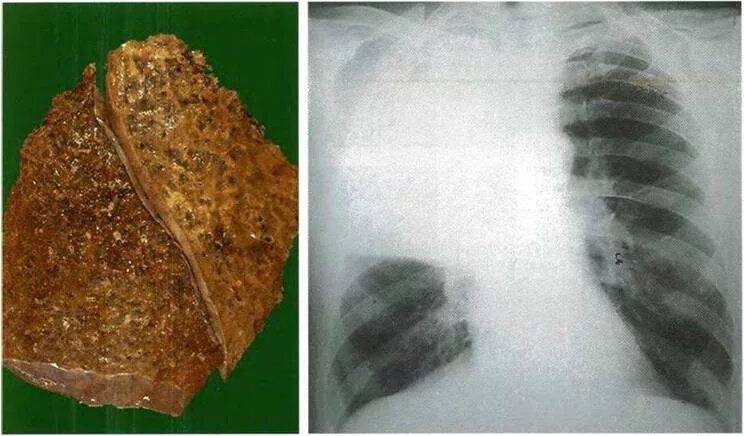

Сильная мокрота в легких